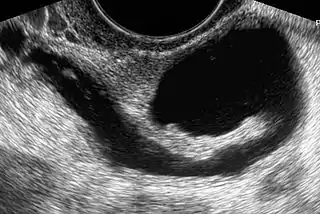

![]() Hidrosalpinx izq. en una ultrasonografía ginecológica | ||

- Ecografía vaginal: este procedimiento permitirá el diagnóstico de los hidrosalpinx de gran tamaño, mediante la observación de líquido acumulado en el interior de la trompa